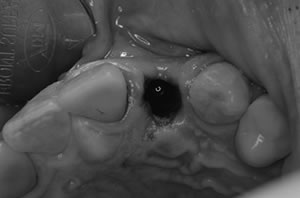

CT像です。歯根の周りには骨がありますので、抜歯即時インプラント埋入の適応です。

抜歯は周りの骨を損傷しないように、普段の抜歯より細心の注意を払います。

抜歯即時のときは、相性の良いHAインプラントを使用します。

また抜歯即時で難しいのは、インプラントの埋入方向が0,5mmでも悪いと形の良いインプラントの被せものができず、抜歯したところに骨がないので初期固定(初期の安定性)に十分注意を払う必要があります。